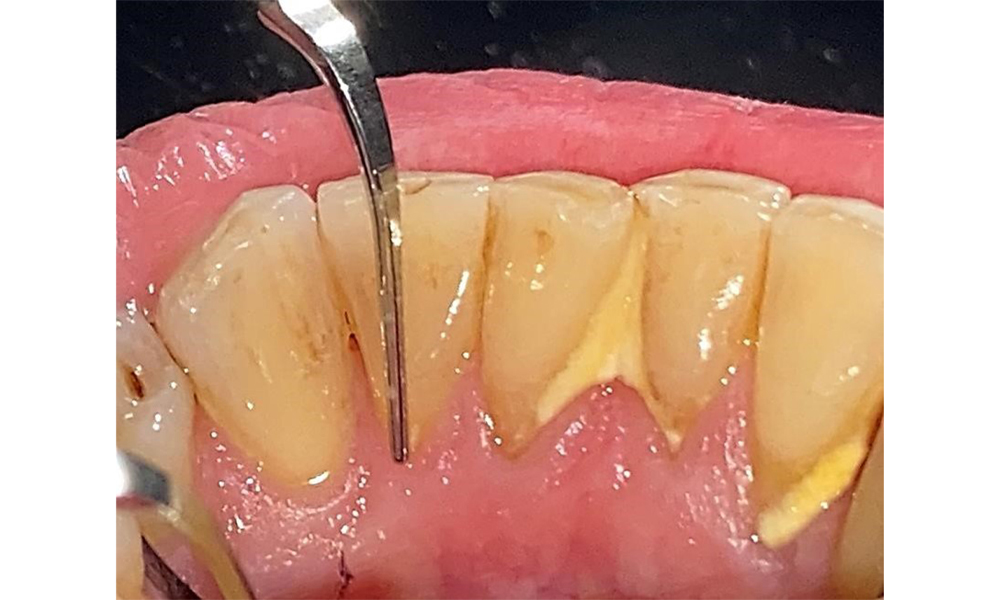

Pacientul prezintă dentiție completă cu 28 de dinți, care include obturații din amalgam și compozit pe molari și premolari. Există un spațiu marginal clinic vizibil la 14. Molarul 27 prezintă un inlay din aur adecvat. Se observă, de asemenea, atriții și abrazii generalizate. (Fig. 2, Fig. 3, Fig. 4, Fig. 5, Fig. 6)

Pacientul prezintă boală parodontală în stadiul II, gradul B (5). Profunzimile clinice de sondare observate, între 1 și 3 mm, se încadrează în limitele fiziologice. Localizat, s-au observat profunzimi de 5 mm, la nivel meziopalatin, atât pe 17, cât și pe 27. Se constată recesiuni generalizate de 1-3 mm, cu pierderi parțiale ale papilelor interdentare (Fig. 2, Fig. 3, Fig. 4)